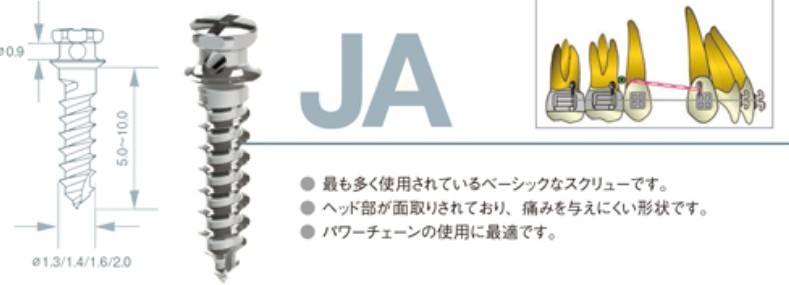

歯科矯正用アンカースクリューを用いた矯正歯科治療

歯科矯正用アンカースクリュー:固定源

歯科矯正用アンカースクリュー

歯科矯正用アンカースクリュー製品仕様:プロシードJAを引用

1) 外科矯正の適応の一部ではあるものの、顎切りをしなければいけなかった患者さんの回避処置

2) 歯を抜くかどうかボーダーにある患者さんの回避処置

3) 良い治療結果を生み出すために必要な顎外装置(お口の外に出る装置・お顔や頭にかぶる装置)を使わないで済ませる回避処置